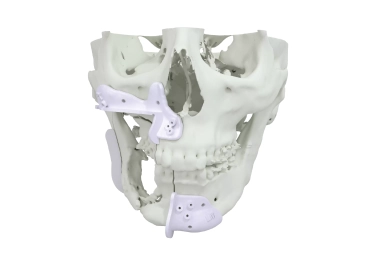

Guias de osteotomia personalizados

Os Guias de osteotomia personalizados são dispositivos indicados para procedimentos cirúrgicos craniomaxilofaciais planejados e possuem a finalidade de transferir um plano pré-operatório para a cirurgia. Eles orientam e/ou auxiliam o cirurgião a realizar osteotomias, furações e marcações no osso conforme o planejamento pré-operatório, incluindo a implantação de produtos customizados ou standard determinando a posição destes em procedimentos cirúrgicos craniomaxilofaciais, como por exemplo, cirurgias ortognáticas e reconstruções.

- Fabricados em poliamida

- Altíssima precisão, fornecendo uma adaptação à anatomia do paciente

- Modelos para osteotomia Lefort, osteotomia e posicionamento de mento, osteotomia mandibular e maxilar, extração de enxerto para cirurgia de reconstrução microvascularizada, ostetomia e posicionamente craniano